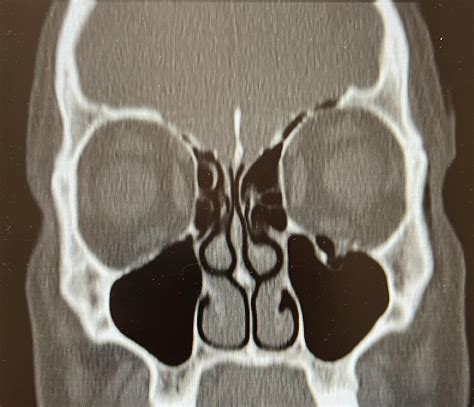

To accurately diagnose an orbital floor fracture, healthcare providers rely on a combination of physical examination and advanced imaging. During the physical exam, a surgeon will test the range of motion of your eyes and check for nerve sensation in the face. To confirm the diagnosis, the gold standard is a Computed Tomography (CT) scan of the orbits.

CT Scan (Coronal View) Best visualization of the orbital floor and sinus involvement.